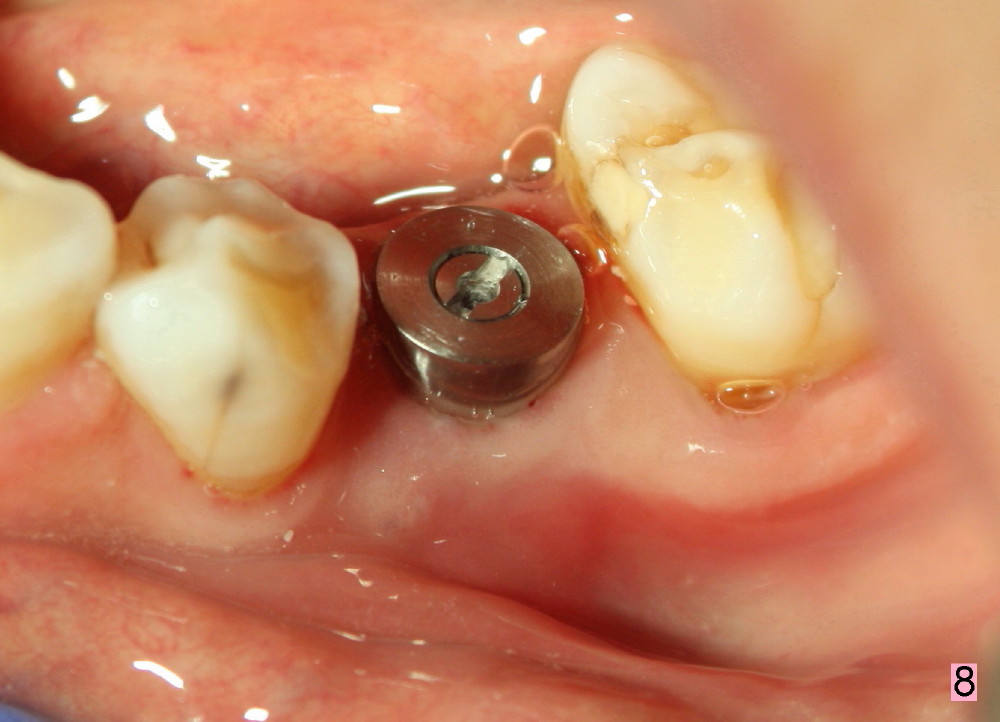

A 54-year-old lady has poor dentition. She seeks treatment because of pain associated with tooth fracture in the lower left 2nd premolar (Fig.1 arrow). The best option seems to be extraction and immediate implant. Thorough curettage after extraction is a key to get rid of infection.

Taking multiple intraop X-ray is also necessary for depth adjustment (Fig.3-5). For example, when a 5x20 mm tap is inserted at the depth of 17 mm, it is close to the mental loop (Fig.4), whereas the binding to the bone is minimal. So a larger implant is to be placed at a shallower depth (Fig.5: 6x17 mm with insertion torque >60 Ncm). The shallower implant placement creates limited space for future abutment and crown (Fig.6,7). A short abutment will be used and the implant margin will be prepared as low as possible. As expected, the wound heals in a week (Fig.8).